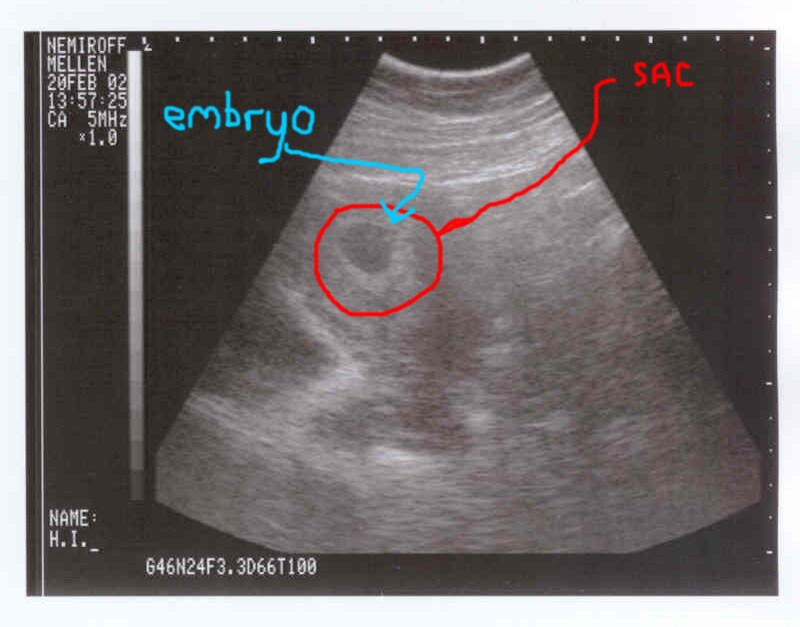

妊娠検査薬は「妊娠」ということだけがわかるだけで他の事はわかりません。よって妊娠検査薬で陽性が出たら次はドクターのところに行って超音波検査をする必要性があります。妊娠反応が出ても子宮外妊娠の場合や流産の場合もあるので、ドクターと話をしてその後のケアが大事となります。

妊娠初期の超音波画像です。クリックしたら大きくなります。 |